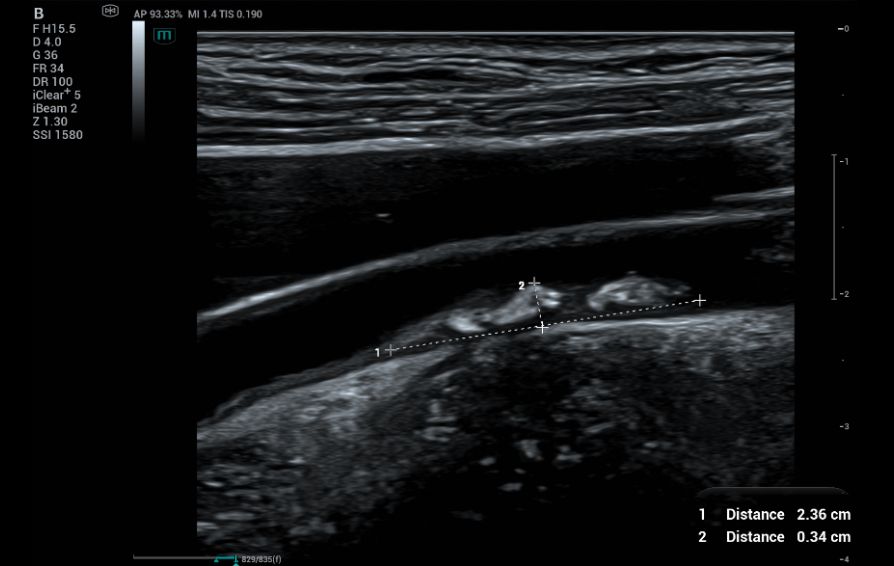

A 50-year-old female came for health screening with no symptoms. Carotid ultrasound assessment was done bilaterally. A plaque measuring 2.36 x 0.34 cm (Figure 1) was found on the right distal CCA.

B mode and CF images of the right carotid plaque.

Fig.1 and 2: B mode and CF images of the right carotid plaque.